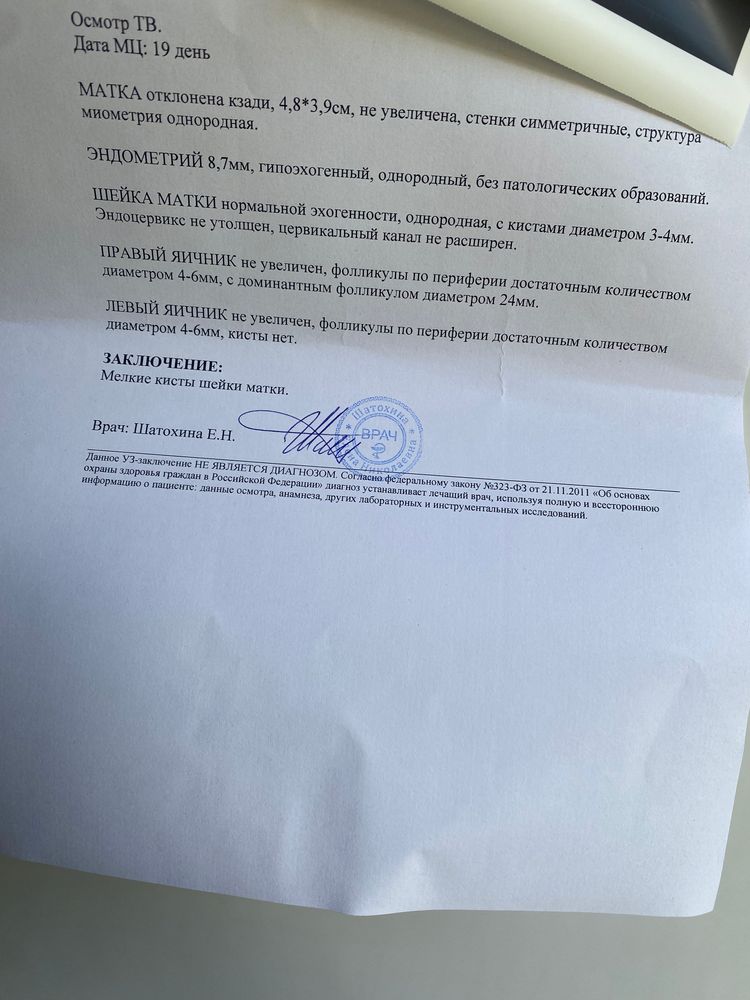

Ходила получается вчера и вот так, сказала врач, что в течение 1-3 дней будет О, цикл 32-35 🙂